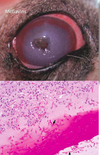

Corneal endothelial dystrophies

Inherited; breed predilections

Old age change

Bilaterally symmetrical foci of opacity which progress to diffuse opacity

Endothelial degeneration of unknown cause

It’s a gross diagnosis! - no histo!

MDx: diffuse corneal edema

Puppy that survived the acute phase of infectious canine hepatitis (CAV-1 infection); immune complex deposition in corneal endothelium

“Blue Eye”

What is the most likely cause of the corneal opacity?

Glaucoma